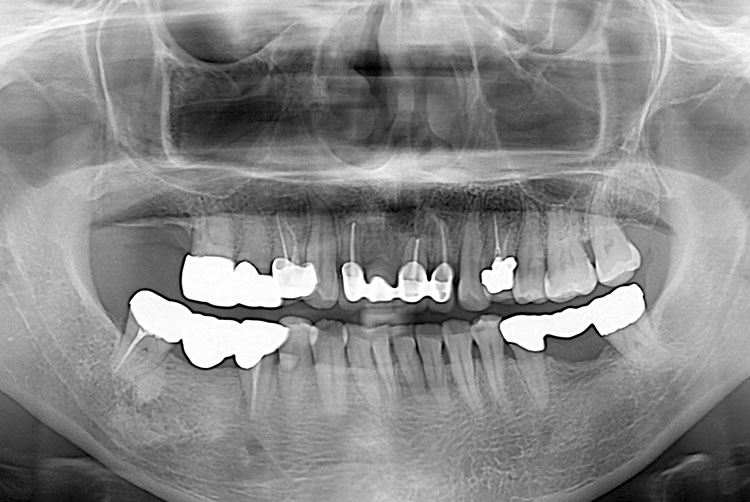

0dd1964d1a1511b88c9d9737e1846398.jpg

치료전 : 2015-05-27